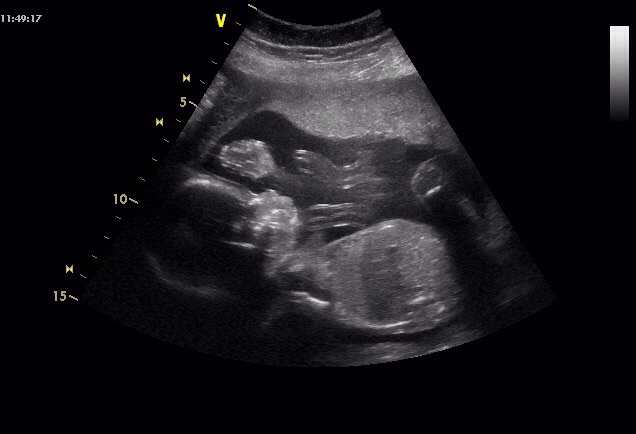

Hezké ráno -) včera jsme byli na screeningu a čekáme chlapečka .jsem 20+4 a prcek je prý podle tabulek 348g a krásně fotky jsme dostali .Prikladam